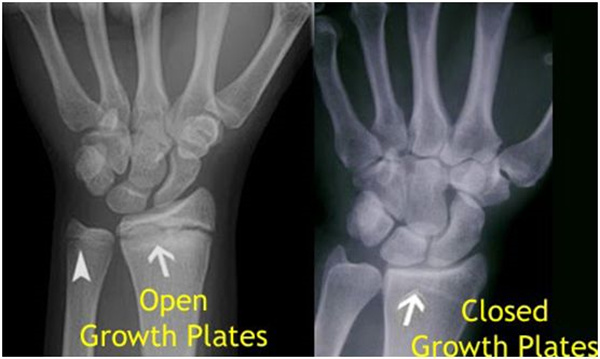

其實想要了解孩子的生長發(fā)育情況或者說孩子未來身高的趨勢,測骨齡是個好辦法。臨床上通常拍攝兒童的左手正位X光片 , 采用《中華-05》骨齡標準對手腕骨發(fā)育程度進行骨齡評價。

我們都知道,人體的高矮是由骨骼的生長發(fā)育決定的,特別是下肢長骨。長骨呈長管狀,在長骨的兩端有一種專管骨骼生長的骺軟骨,它與干骺端之間有一盤狀軟骨結構稱為骺板(線),在幼兒的X光片上表現(xiàn)為一條較寬的透光帶。(見下圖)

未成年時隨著年齡的增加骺軟骨端不斷骨化,骨骼就不斷增長。當骨骺線完全閉合時骨骼就停止生長,個子也就不再增長了。一般骨骺端完全閉合的年齡是18~20歲左右。

讀到這里,可能很多人又會有這樣一個疑問:骨骺線會不會提前閉合呢?

答案是會的。

骨骺線提前閉合最多見的情況是性早熟,而這也是很多醫(yī)生專家建議孩子進行骨齡測量的原因之一。另外,在兒童時期大量補鈣也會使骨骺端提前過早閉合。